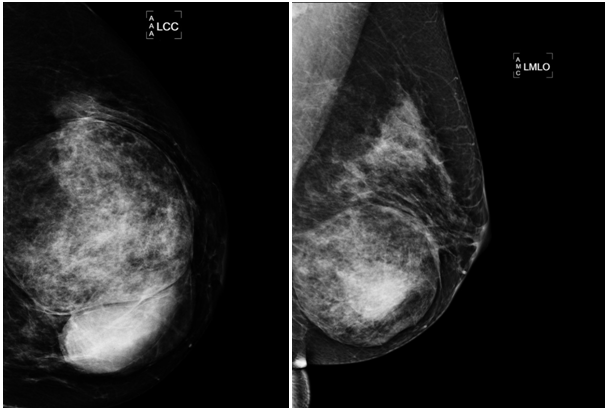

A 47year-old woman with history of a long standing palpable mass on the left breast, which was biopsied on 2006 resulting in hamartoma. She had first degree familiar history of breast cancer with her mother diagnosed younger than 50 \years of age and who later on died of that cause. The patient presented to our office, in June 2016 for progressive growth of her breast tumour. At examination her breasts were fibrous, with a palpable firm and mobile breast mass, not fixed to skin, of 8x6x5cm on the left LIQ, and another large, soft and well defined mass in left LOQ and UOQ of 10x10x5cm, There were no palpable masses in the axilla. On mammography there was a radiolucid well defined breast mass in the left LOQ and UOQ, which was stable in size and shape regarding prior mammogram of twoyears. A new dense, oval and partially defined breast mass was evident in the LIQ (Figure 1). The latter on breast ultrasound corresponded with a hypoechoic and heterogenous nodule with partially defined margins, which measured approximately 7cm. The first lesion was heterogenous and hyperechoic, measured more than 8cm, and was the previously biopsied nodule (Figure 2). She later on underwent a breast MRI that showed a round mass in the LIQ, which was hyperintense in T2, hypointense in T1, had a homogenous enhancement with a plateau curve. In the LOQ there was a well-defined mass, which was heterogenous with fibrous and fatty tissue, and did not enhance with gadolinium (Figure 3). A core biopsy of the two masses was then performed, demonstrating a biphasic fibro-epithelial lesion compatible with a PT at the LIQ, and fibrocystic changes and intraductal hyperplasia without atypia at the LOQ. On August 2016, the patient underwent a partial mastectomy, without incidents, and was sent home on the subsequent day (Figure 4). The definitive biopsy demonstrated that the tumour at the LIQ corresponded to a malignant PT (Figures 5) (Figure 6), and that the LOQ mass was a large breast hamartoma (Figures 7 & Figure 8). Posteriorly, she received 25 radiotherapy fractions, without major adverse effects. She was recently controlled with breast ultrasound and MRI that showed no residual breast lesions.